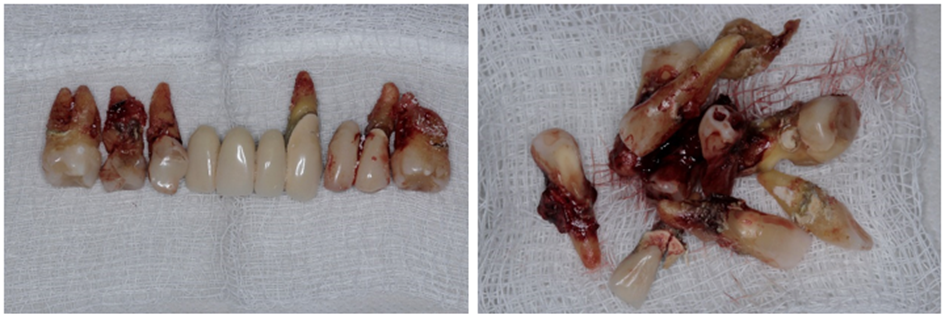

Diante dos exames foi proposto ao paciente a extração de todos os dentes remanescentes, instalação de implantes na maxila e mandíbula e duas próteses totais provisórias durante o período de osseointegração.